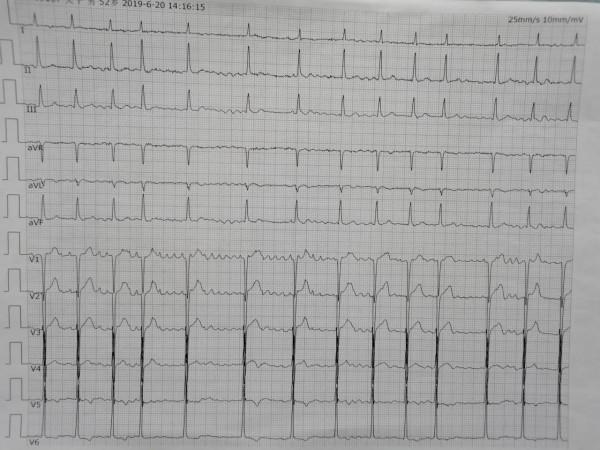

心電圖特點:

1.是正常 P 波消失,代以大小不等、形狀各異的質動波(波)。通常以 V 1導聯為最明顯;房顫波的頻率為350-600次/分。

2.心室律絕對不規則, QRS 波一般不增寬。

3.若是前一個 RR 間距偏長而與下一個 QRS 波相距較近時,易出現一個增寬變形的 QRS 波,此可能是房顫伴有室內差異傳導,並非室性期前收縮,應注意進行鑑別(圖4-1-62)。

標註的1、2、3的長短距離不一,指的就是所謂R-R間期不等,也就是房顫形成心室律絕對不規則。

如何從心電圖上判定診斷出心房顫動呢?

一份心電圖拿過來,先看一下,心室波跳動的是不是很不齊?(就是R-R間期不等)

如果R-R間期很不等,就要想到診斷是“房顫”的可能了。

那麼,繼續去尋找,最長的那個“R-R間期”,看最長那個R-R間期中間是不是有很多的形態不一、大小不等“抖動”的波形(心房顫動波)。

標註1即所謂最長R-R間期,標註2是形態不一大小不等的顫動波

如果是的話,這份圖的診斷:心房顫動,已經百分之九十成立了。

最後,再去尋找檢視,圖中其他特徵是否符合房顫的心電圖表現特點,基本符合的話,診斷就完全成立了。

題目:下面那張心電圖都有哪些診斷呢?